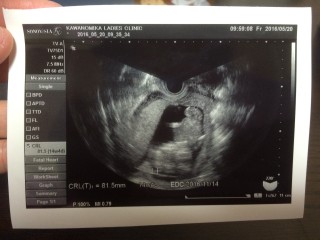

悪阻も治まりつつある中での検診。この日は寝てたのかあまり動いてはいませんでした。しかも背中を向けて、左手を耳の辺りに当てていて顔が見えませんでした(;_;)一緒に見ていた娘も顔が見えなかったので微妙な反応(笑)赤ちゃんの大きさは8.4cmで、順調でした。

BPD2.73cm